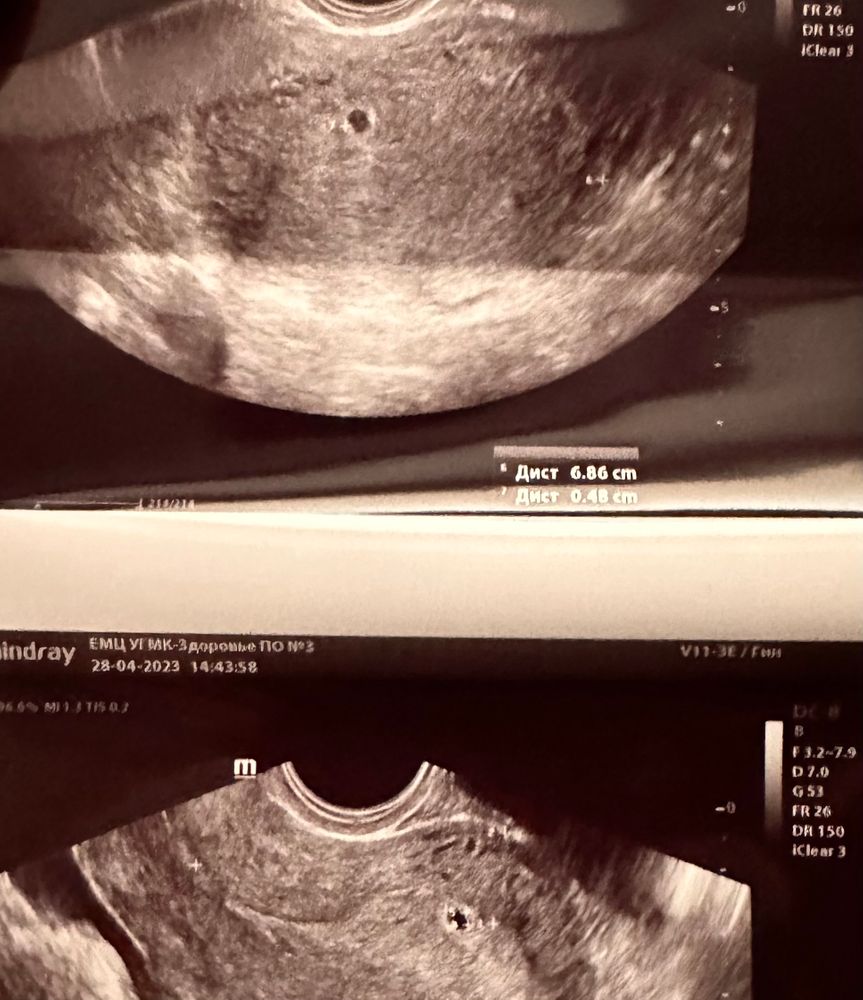

Там есть вроде чёрный кружочек небольшой, похож на плодное яйцо. Но эмбриона пока не видно.

Фрау Макыздя, вот именно пятно на котором стоит измерение размера мне кажется никак не похож на плотное яйцо

Galina, вот то, которое с размерами, хрен знает вообще что это. Но выше от него чёрное пятнышко, оно похоже на плодное яйцо на 4-5 неделях.

Не вижу никакой Б, что то другое измерено, вообще на яичник похоже с фолликами и какими то включениями 🤷♀️

Просто со своим УЗИ сравниваю

Так выглядит плодное яйцо на очень маленьком сроке 4недели .

Вот так выглядит плодное яйцо. Так что думаю тут обман

Да, похоже на плодное яйцо. Ранний срок совсем

Matimacheha, разве плодное яйцо можеть иметь такую эхогенность что выглядит как пятно? Честно, я поэтому в недоумении потому что весь инет узи раннего срока перешарила но такое вижу такое впервые среди кучи узи плодного яйца раннего срока такого пятна ни разу не встречала🤔🤔🤔🤔

Больше похоже на полость или очаги эндометриоза, аденомиоза. Фолликул и жт внутри полые (чёрные цветом), рваные края.

Есть маленькие чёрные точки, похожие на фолликулы. Поэтому это яичник скорее всего, а не плодное яйцо.

Похоже на измерение эндометрия